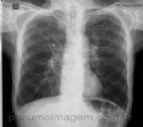

Mesa redonda no CHEST 2015 revisou o diagnóstico e o tratamento das principais formas de aspergiloses pulmonares. Resumimos as principais informações referentes à Aspergilose Broncopulmonar Alérgica e à Aspergilose Invasiva. ASPERGILOSE ...